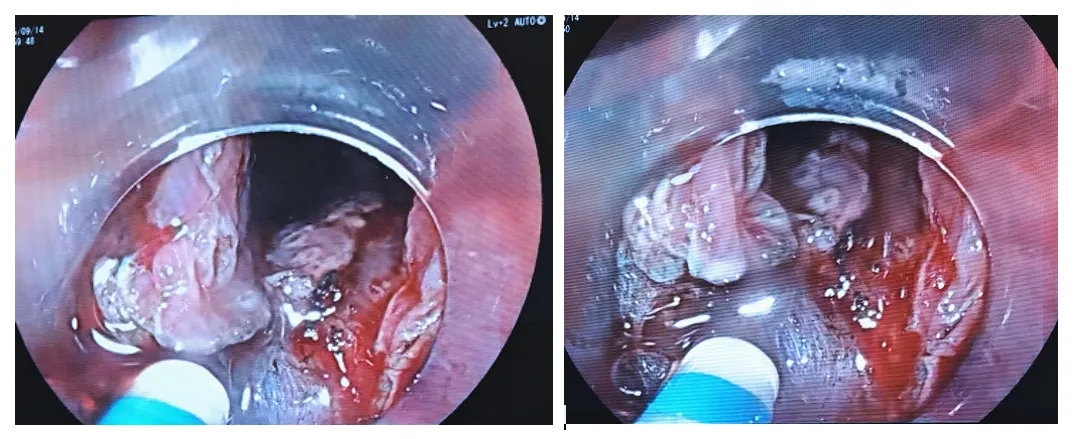

10:56患者是左侧卧位,现在换成平卧位,病灶还是在低位,可能还是需要用到牵引来辅助

10:59把病灶往下推利用重力牵引。

准备进圈套器牵引,用钛夹带圈套器进去夹住病灶口侧拉起来,可拉,可推(牙线太细,没有圈套器那么好效果)

11:06边补水边剥离11:08病灶切下来了。

11:09创面处理,对创面可疑的出血处给予电凝止血